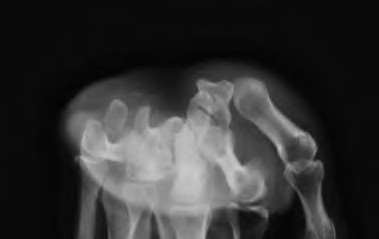

A 50-year-old woman is diagnosed with carpal tunnel syndrome. She is prescribed a cock-up wrist splint at 30 degrees of extension to wear at night. This splint has what effect on the carpal tunnel?